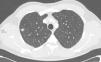

We report the case of a 46-year-old man with terminal chronic kidney disease caused by reflux nephropathy, renal transplant from a cadaver donor 10 years previously, receiving immunosuppressive treatment with prednisone, tacrolimus, and sodium mycophenolate. He attended a routine follow-up visit, where he was seen to be totally asymptomatic, with no suspicious respiratory or infectious clinical symptoms. No significant findings were made on physical examination. Chest X-ray revealed an ovoid lesion in the posterior segment of the right upper lobe (RUL), 12mm in diameter, not observed in the study performed 1 year previously. The lesion was explored in greater depth with a chest CT, which showed a lung nodule suggestive of neoplasm in the RUL (Fig. 1), consistent with stage IA (T1aN0MX). The PET scan showed pathological uptake of this lesion, so malignancy was suspected. The nodule was resected surgically via an atypical segmentectomy with diagnostic and therapeutic intent.